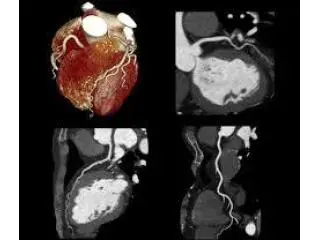

Northside Imaging, located in Mickleham provides advanced CT Coronary Angiography (CTCA) to non-invasively examine the coronary arteries of your heart with stunning precision and rapidity. With the most advanced technologies for imaging, our experienced team offers accurate information about the health of your coronary arteries, helping to identify obstructions and assist in making the treatment process with ease and confidence. For patients looking for an extensive cardiac examination, CTCA at Northside Imaging provides precise results within a friendly and patient-focused. Learn more at northsideimaging.com.au.